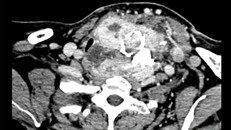

Cắt khối u bướu cổ khổng lồ cho người phụ nữ 26/05/2019 13:59 (Ngày Nay) - Khối bướu cổ đã được được phát hiện từ nhiều năm trước nhưng chỉ sau khi bị nghẹn thở, khó thở, bệnh nhân mới vào viện và được chỉ định mổ. Ca mổ thành công, khối u lấy ra nặng hơn 1kg.